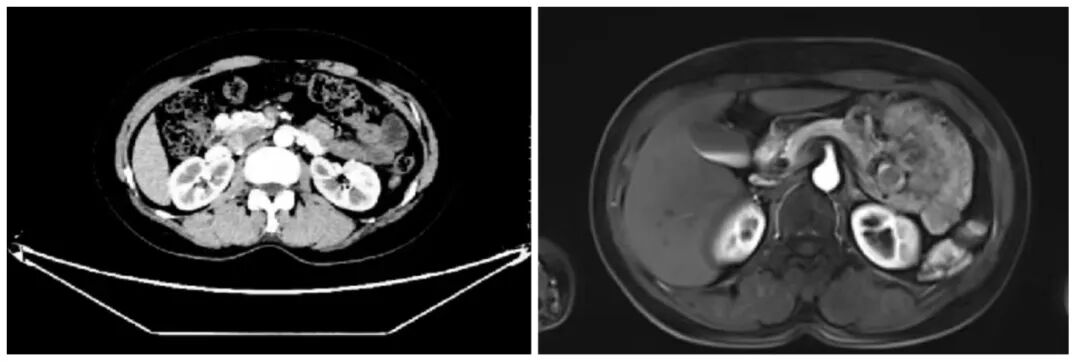

近三个月来,朱女士的生活被一层无形的阴影笼罩。突如其来的头晕、双手不受控制地颤抖、眼前发黑直至晕厥抽搐——这些症状如影随形,让她饱受折磨。辗转多家医院,却始终找不到病因。直到她走进柳州市中医医院普通外科一病区(肝胆胃肠胰腺外科),谜底才终于水落石出:胰腺头部深处,两枚神经内分泌肿瘤(胰岛素瘤)正悄然释放过量胰岛素,引发严重的低血糖症状,如同在体内埋下了一颗“定时炸弹”。

面对这个位于胰腺头部的复杂肿瘤,传统的胰十二指肠切除术需要切除多个重要器官,创伤大、恢复慢,将严重影响患者未来的生活质量。但普通外科团队经过周密评估及与患者、家属充分沟通后,毅然选择了一条更为艰难却充满温度的道路——实施“保留十二指肠的胰头肿物切除术”。

在郑捷主任医师的带领下,胰腺外科手术团队凭借对胰腺解剖结构的深刻理解,在精密影像导航的护航下,展开了一场精准的“生命拆弹”。他们小心翼翼地分离组织,如同在精密的钟表内部进行维修,既要完整切除肿瘤,又要保护好每一根血管、每一个相邻器官。当两枚肿瘤被成功取出时,手术室里所有人都松了口气。